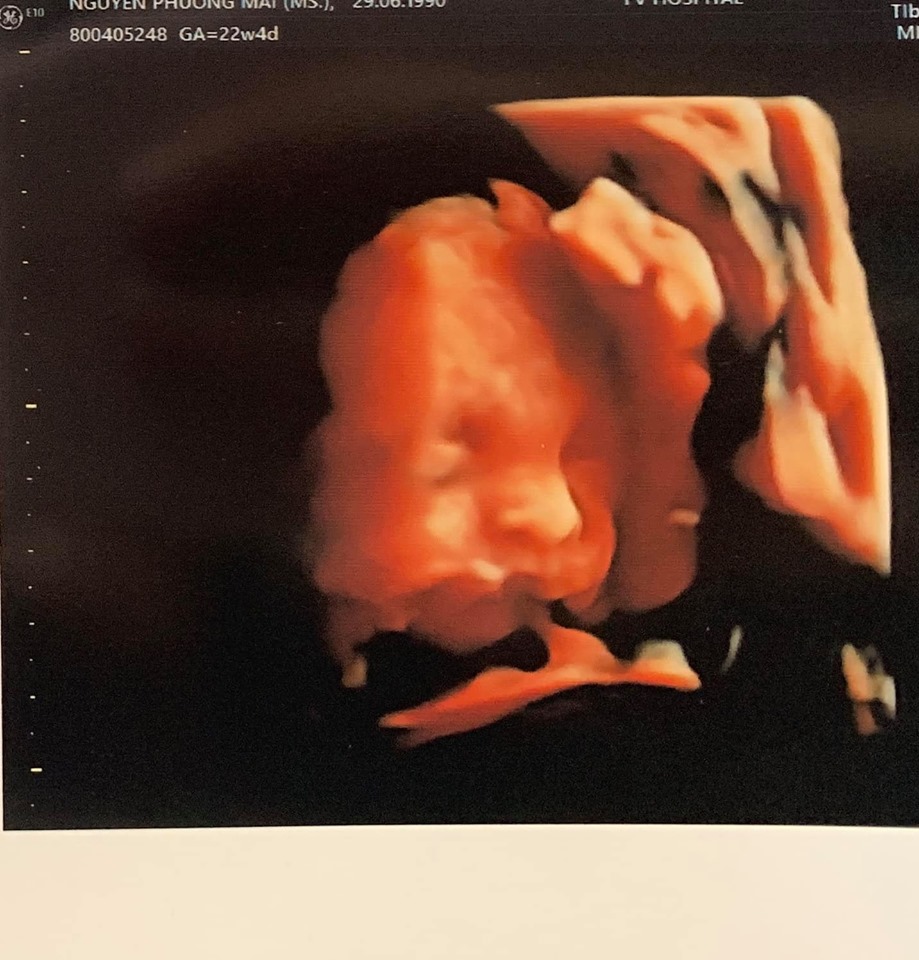

Sau khi kết hôn với ông xã ngoại quốc Marcin Miller vào ngày 15/6 và liên tục phủ nhận nhiều lời đồn đoán về chuyện bầu bì thì vào đầu tháng 8 vừa qua, nữ MC kiêm siêu mẫu - Phương Mai cũng chịu thông báo tin vui của mình tới người hâm mộ bằng việc chia sẻ hình ảnh siêu âm cùng vòng 2 nhô cao đồng thời tiết lộ đang mang thai ở tuần thứ 23.

Và cô còn khoe luôn cả ảnh siêu âm đứa con đầu lòng của mình